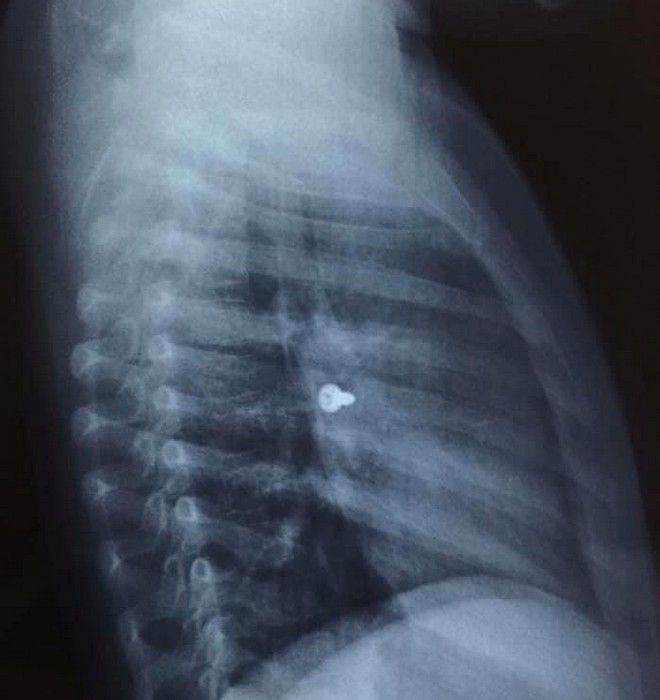

Απίστευτες μοιάζουν οι εικόνες από τις ακτινογραφίες ενός 3χρονου κοριτσιού από την Κρήτη που κατάπιε βίδα, η οποία κατέληξε στον αριστερό του πνεύμονα.

Σύμφωνα με τα όσα έκανε γνωστά ο αναπληρωτής καθηγητής ΩΡΛ της Ιατρικής Σχολής Κρήτης, Μανώλης Προκοπάκης, το συμβάν έγινε την Τρίτη. Το άτυχο 3χρονο κορίτσι μεταφέρθηκε άμεσα σε νοσοκομείο του Ηρακλείου. Αμέσως έγιναν οι απαραίτητες ακτινογραφίες που έδειξαν πως η βίδα βρισκόταν στον αριστερό πνεύμονα του παιδιού.

Ο καθηγητής κ. Προκοπάκης σε ανάρτησή του στα στο Facebook ανέφερε: “Πολύ επείγον χειρουργείο! Πριν από λίγο. Αφαίρεση βίδας από αριστερό βρογχικό δέντρο τρίχρονου κοριτσιού. Πολύ επικίνδυνο…”.